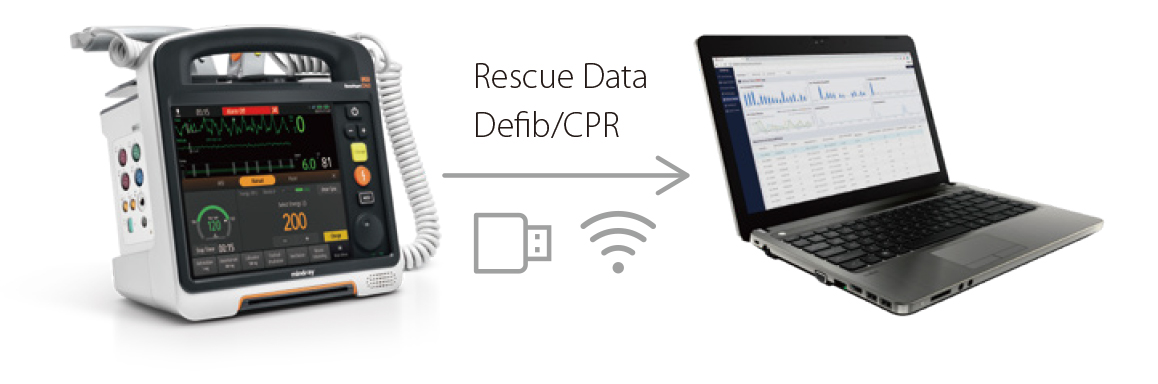

- Die strukturierten Nachbesprechungsprotokolle des D60 verbessern die Leistung der Reanimationsteams bei nachfolgenden Reanimationseins?tzen.

- Mit dem Trainingsmodus des D60 k?nnen Sie praktische Erfahrungen mit der Bedienung sammeln.

Strukturiertes Debriefing

- Die strukturierten Nachbesprechungsprotokolle des D60 verbessern die Leistung der Reanimationsteams bei nachfolgenden Reanimationseins?tzen.

Praxistraining

- Mit dem Trainingsmodus des D60 k?nnen Sie praktische Erfahrungen mit der Bedienung sammeln.